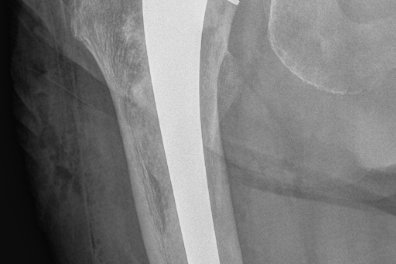

Figur 2 viser røntgenbilder av en hofte med artrose (figur 2a til venstre) og en hofte som har fått en sementert hofteprotese (figur 2b til høyre).

I prinsippet består en hofteprotese av en stamme som går ned i lårbenet, et hode som settes på toppen av stammen som erstatning for lårbenshodet, og en kunstig hofteskål (koppen) (figur 1). Forskjellige stammer kan kombineres med kopper av forskjellige merker, slik at kombinasjonsmulighetene blir svært mange.

De usementerte protesene er vanligvis laget av titanium og har enten en overflatestruktur eller et overflatebelegg som gjør at bein kan gro fast på protesen. Begge deler kan fungere godt i forhold til å få protesene til å sitte fast.